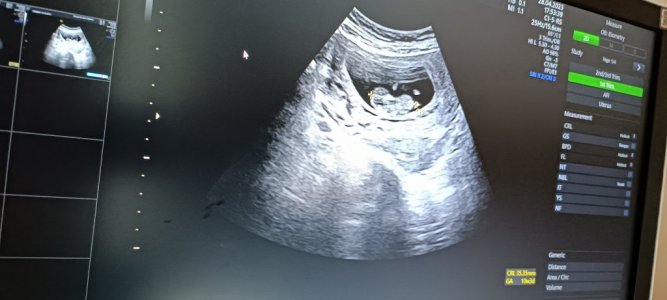

Cinsiyet tahmini yapabilir misiniz?